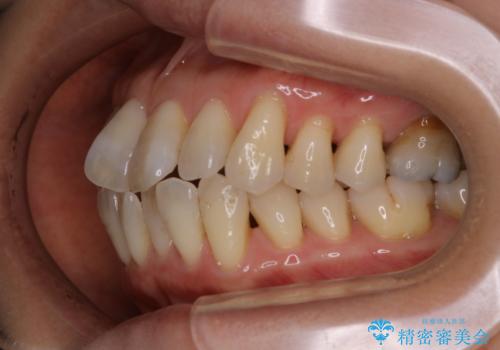

IPRのメリット・デメリットについて

IPRを行うことによるメリットとして、

➀歯を抜かなくても済む

②骨や歯ぐきが薄いケースで骨、歯ぐきを守ることができる

③期間が短くて済む

IPRを行うことによるデメリットとして、

➀歯を削ることが出来る量には限度があるため、再矯正治療を行う場合にIPRを選択できなくなる可能性がある

②歯が少しだけ小さくなる

以上のことが挙げられます。

限度を守って歯を削ることで、知覚過敏が起きたり、虫歯になりやすくなるということは起きません。

また、無理に並べるよりも歯を削って並べることで骨、歯ぐきが守られ、

結果的に歯の寿命も長くなります。